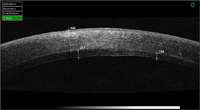

Figura 2), opacidades corneales estromales y su profundidad, patologías asociadas al LASIK (

Figura 3 y

Figura 4, fase infecciosa de una queratitis estromal en la interfase y posterior resolución) y desprendimientos de la membrana Descemet, entre otras muchas patologías.

Figura 3. Infección en operado de LASIK.